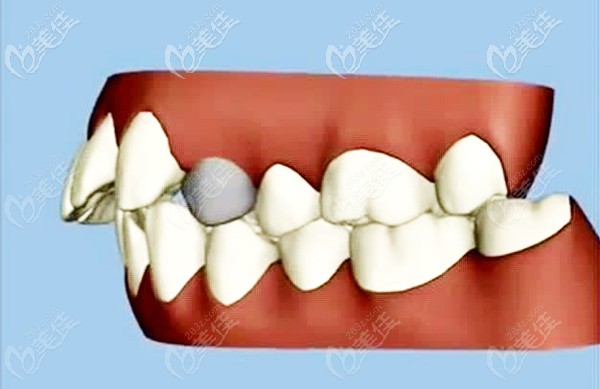

當(dāng)正畸醫(yī)生宣布你需要拔掉多顆正畸牙后,才能做矯正,此時(shí),是不是好擔(dān)心拔牙矯正會不會出現(xiàn)什么后遺癥?來看看真相是怎樣的....... b1606 G0 V0